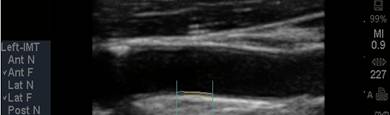

The CIMT procedure is

simple. An ultrasound study is carried out of the carotid arteries in your

neck. A specialized software program is used to precisely measure the mean and

maximum IMT. Standard carotid ultrasound is looking for “flow-limiting”

stenoses, narrowings that could be addressed surgically. This is not what we

are interested in with CIMT testing - we will be measuring soft plaque

accumulation in non-overtly diseased vessel segments (if plaque is identified we

measure the CIMT at an adjacent, normal appearing segment). While the presence

of plaque obviously has significance, it is the IMT parameter that best predicts

the presence and severity of atherosclerotic vascular disease elsewhere in your

body, it’s risk of progression, and your risk of sustaining an atherosclerotic

event (think of IMT as the “staging ground” for obstructive plaque – the higher

the IMT, the greater the rate of IMT progression, the more rapidly will large,

obstructive plaques form). Over 2,000 studies (go to www.pubmed.gov and enter

Carotid IMT) document the link between CIMT and current risk, and an even more

powerful relationship between the rate of change in CIMT and future risk. We

will use CIMT to help us decide who should be treated with preventive measures

and how aggressive our efforts should be. We will use the rate of change of

CIMT to gauge the success of the regimens that we construct for you.